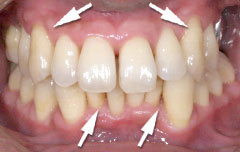

初期の歯周病の治療

| 歯茎にプラーク(歯垢着が)と歯石の沈認められます。歯肉が腫れ、出血がありました。 | 歯科衛生士の治療と、ブラッシング技術の向上により、歯茎が引き締まり健康的な状態になりました。 | |